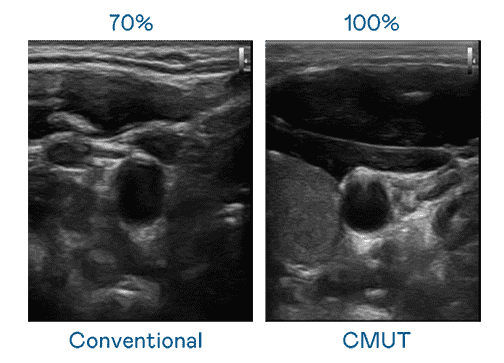

CMUT 技术是一种用电容式微机电元件来产生超音波讯号的技术。。与传统 PZT 压电式技术相比,,,CMUT 频宽增加 30%,,更宽频的超音波讯号让影像解析度大幅提升,,,是实现高影像品质医疗超音波扫描、、、促进精准医疗发展的关键技术。。。。

大频宽带来超清晰影像

超音波影像的解析度高低,,,首先取决于探头能发出的讯号频宽。。。z6mg·人生就是博 CMUT 可提供高清晰的超音波讯号,,,,提供高频宽、、、高灵敏度、、影像纹理细节更高的超音波影像,,,,协助医护人员缩短影像判读时间及利用精准的医疗影像进行诊断。。。